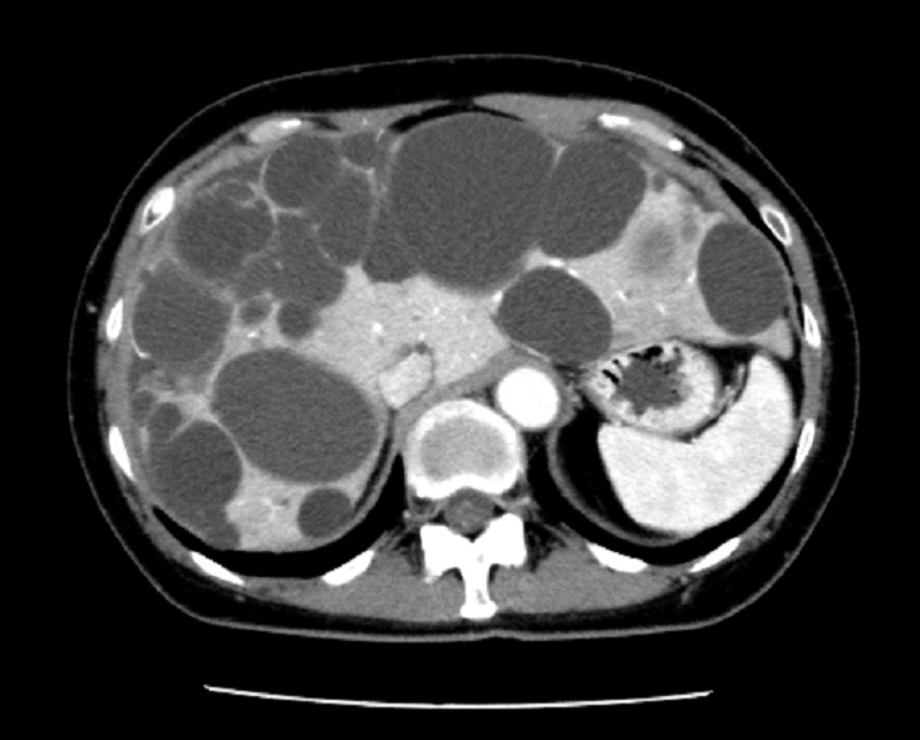

- 多発肝嚢胞